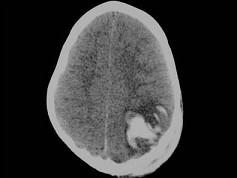

问题 男,3岁,头颅被球击中,请结合CT图像,最选择可能的诊断是 ( )

选项 A、动脉瘤破裂出血 B、血管畸形 C、脑结核 D、脑挫裂伤血肿形成 E、高血压性脑出血

答案 D